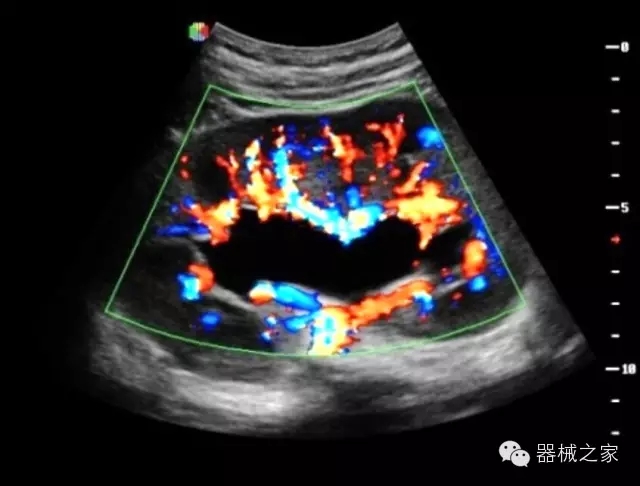

臨床圖片賞析

·獨(dú)有的HoloTM PW 實(shí)時(shí)3取樣門PW成像技術(shù),精確進(jìn)行血管診斷;